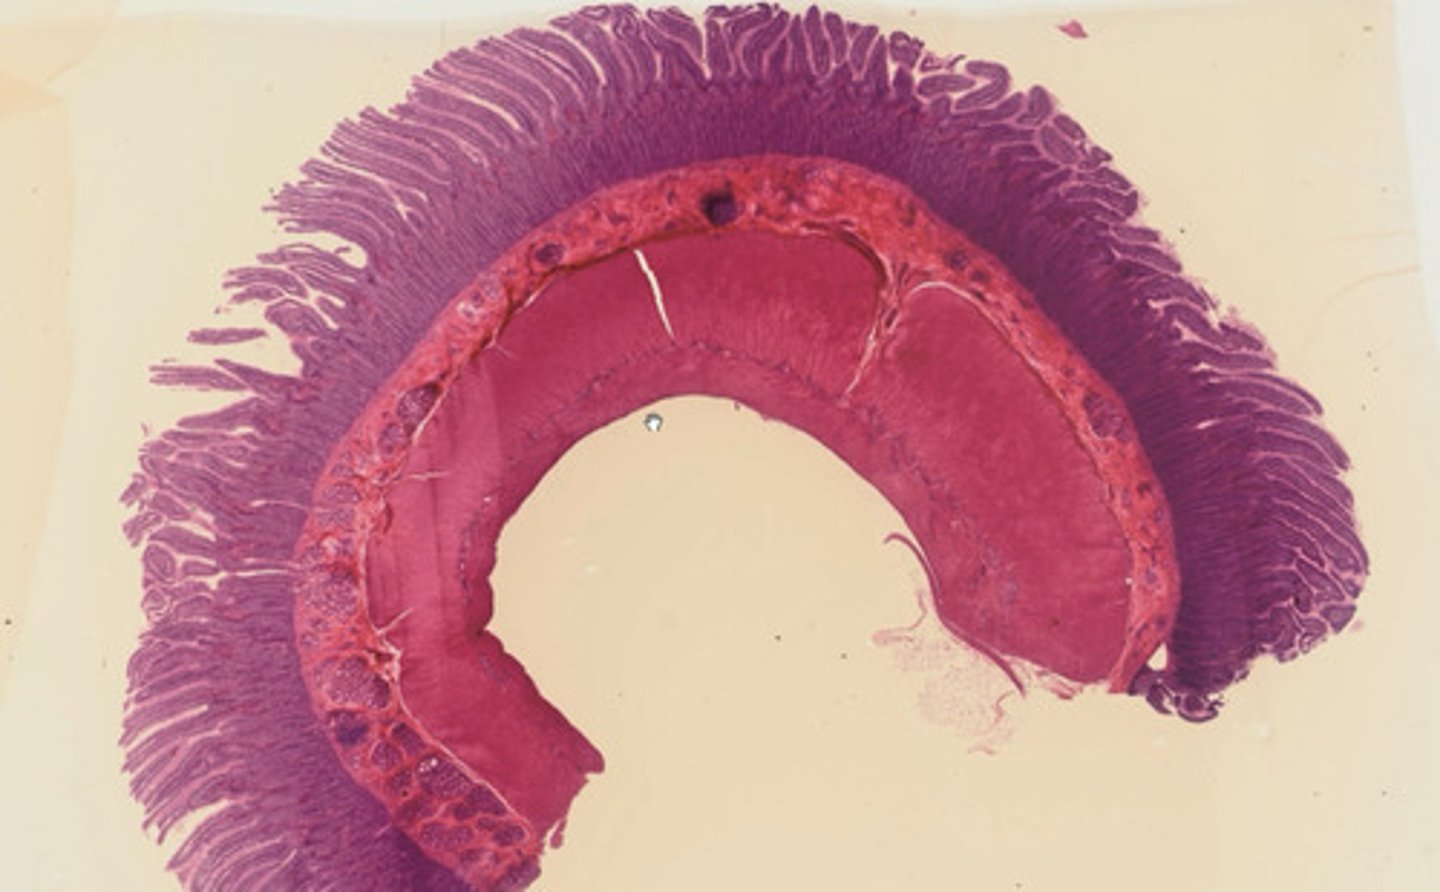

Jelito cienkie - dwunastnica (H+E)

Jelito cienkie - kręte (H+E)

Jelito grube (H+E)

Wyrostek robaczkowy (H+E)